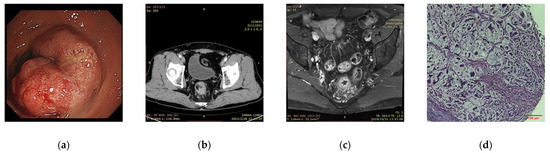

- Diagnosis: The qualitative diagnosis and staging of CRC mainly rely on radiography and pathological examination [5]. Thanks to advanced processing technology in the field of image recognition, DL can significantly improve medical image readability, eliminate differences in experience, and reduce misdiagnosis rates.

4. Applications in CRC Diagnosis and Staging

4.1. Pathological Diagnosis

4.2. Radiological Diagnosis